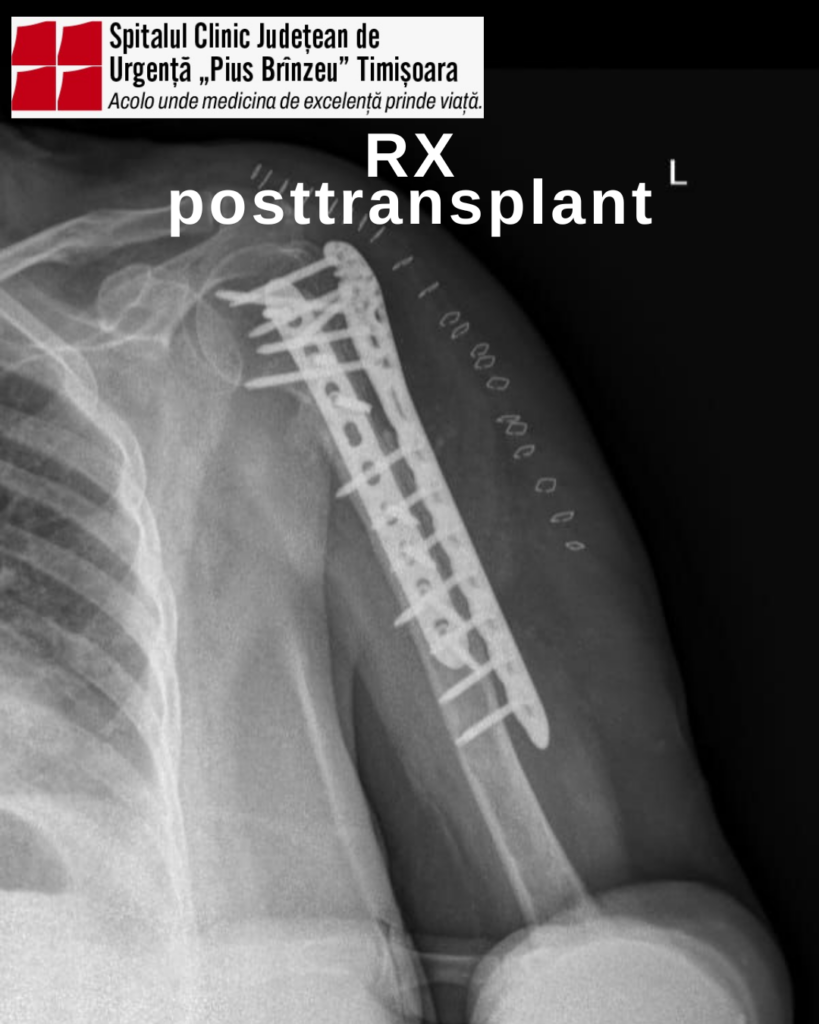

Astfel, chirurgii au realizat o augmentare biologică cu alogrefă structurală de peroneu, urmată de fixare internă prin tehnica „double plating”, procedură modernă, utilizată în centrele de excelență din domeniul ortopediei.

Intervenția a fost realizată de o echipă multidisciplinară, coordonată de conf. dr. Cosmin Faur, alături de dr. Dragoș Troțea, medic primar ortopedie-traumatologie, și dr. Zoran Săndici, medic primar ATI, sprijiniți de o echipă extinsă de medici, asistenți medicali și personal auxiliar.